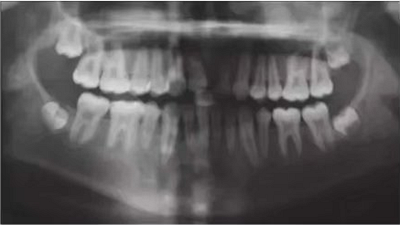

車禍后,一名10歲男孩被送往Shariati醫(yī)院急診科。診斷出上頜中切牙的脫落和側(cè)切牙的嵌入(圖1)。脫落的中切牙丟失了,沒(méi)有進(jìn)行再植。全景片示除第二磨牙外的恒牙列(圖2)。

圖1. 初診口內(nèi)照

圖2. 初診全景片